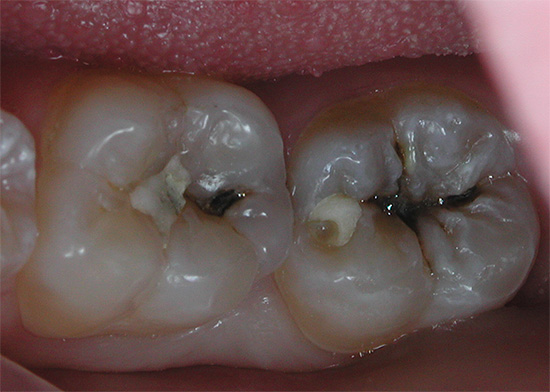

Ed è così che appare il trattamento della carie profonda al microscopio, tutti gli stadi sono ben tracciati